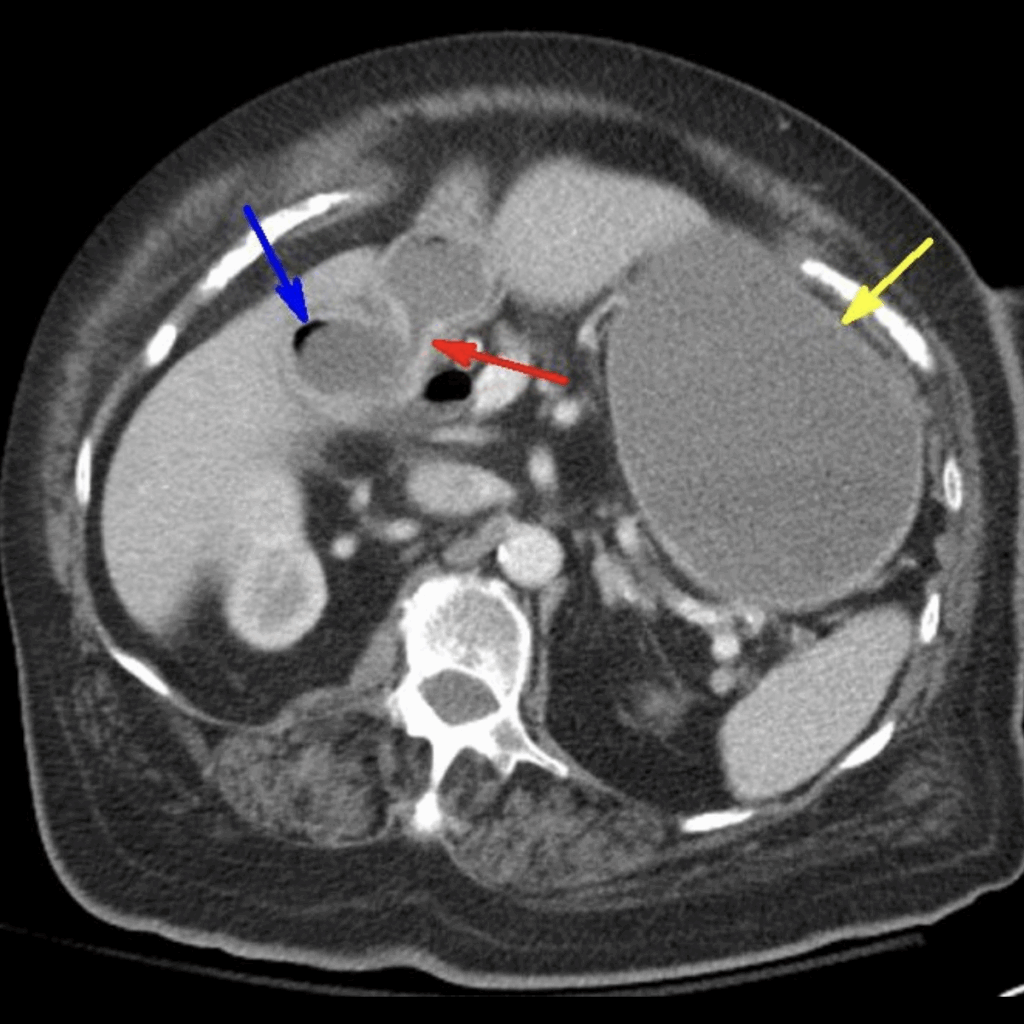

Case 2: Bouveret syndrome with Rigler’s triad: air within the gallbladder (blue arrow), cholecystoenteric fistula (red arrow) with ectopic gallstone in proximal duodenum, and gastric distention (yellow arrow). Radiopaedia